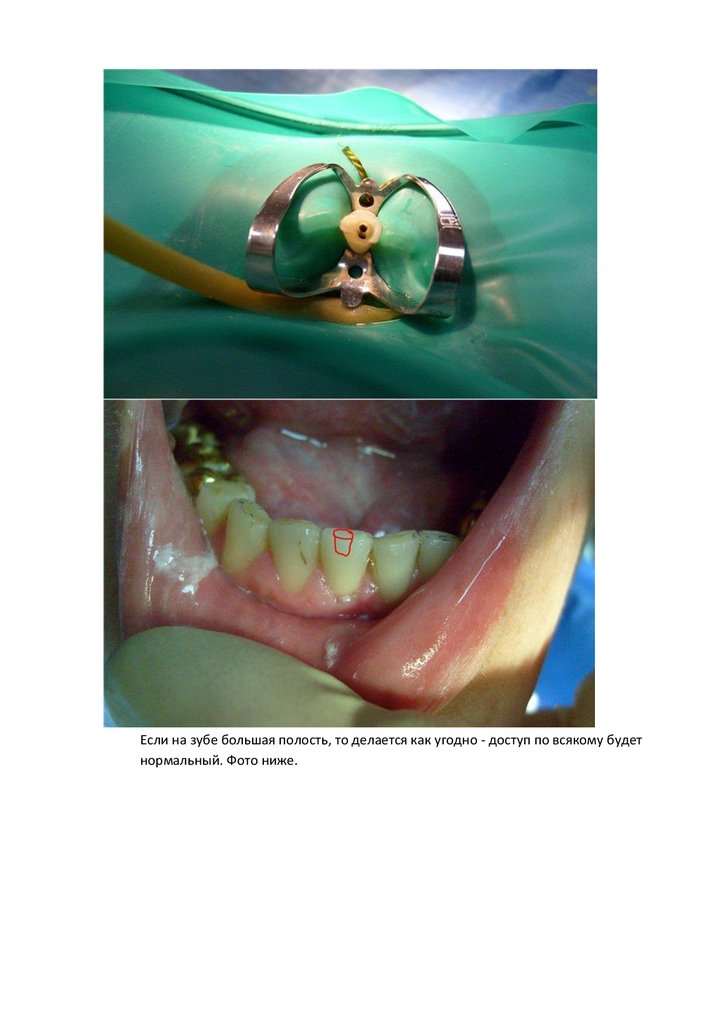

Если на зубе большая полость, то делается как угодно - доступ по всякому будет

нормальный. Фото ниже.

На нижних резцах полость делается по середине режущего края и если присутствует

2 канал (что чаще) то выводится немного на вестибулярную поверхность для

лучшего доступа к язычному каналу. Если полость 3 или 4 класса то полюбому

доступ к каналам приходится выпрямлять и здесь уже практически всегда в проекте